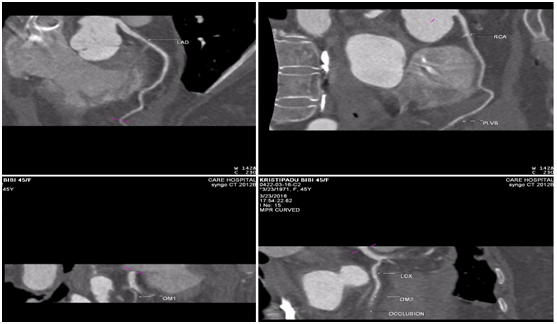

2D Transthoracic Echo showed regional wall motion abnormality in basal and mid inferior wall and inferior septum and basal posterolateral wall, moderate LV dysfunction, preserved RV function, mild MR, moderate circumcardiac pericardial effusion. Her blood analysis was unremarkable. In view of recent onset pericardial effusion post thrombolysis and tachycardia with persistent ST elevations a suspicion of cardiac rupture was entertained. The 2D Echo did not reveal any clue to the cause of pericardial effusion so an additional investigation was sought to clarify this suspicion. Coronary CTA was planned as it is rapid, noninvasive, gives information on coronary anatomy and most importantly with the cine sequences the rupture track is delineated and the contrast pooling in the pericardial space is diagnostic of rupture. Retrospective gated coronary CT scan was performed which revealed a sealed myocardial rupture in the basal posterolateral wall of theleft ventricle with a neck of 2mm and an area of 0.8cm2 (Figure 1). CT coronary angiogram showed total occlusion of a large OM2 branch with grade V thrombus (Figure 2). Coronary anatomy was clearly depicted despite her heart rate being above 100 beats per minute which was corroborated by the coronary angiogram which was done just prior to subjecting her for surgery.

Figure 2 MIP images depicting the coronary anatomy and the occluded OM vessel.